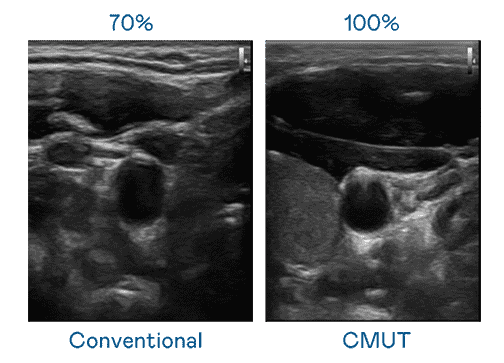

CMUT 技术是一种用电容式微机电元件来产生超音波讯号的技术。。。。与传统 PZT 压电式技术相比,,,,CMUT 频宽增加 30%,,,,更宽频的超音波讯号让影像解析度大幅提升,,是实现高影像品质医疗超音波扫描、、促进精准医疗发展的关键技术。。

大频宽带来超清晰影像

超音波影像的解析度高低,,,,首先取决于探头能发出的讯号频宽。。。赏金国际 CMUT 可提供高清晰的超音波讯号,,,,提供高频宽、、、高灵敏度、、、影像纹理细节更高的超音波影像,,协助医护人员缩短影像判读时间及利用精准的医疗影像进行诊断。。